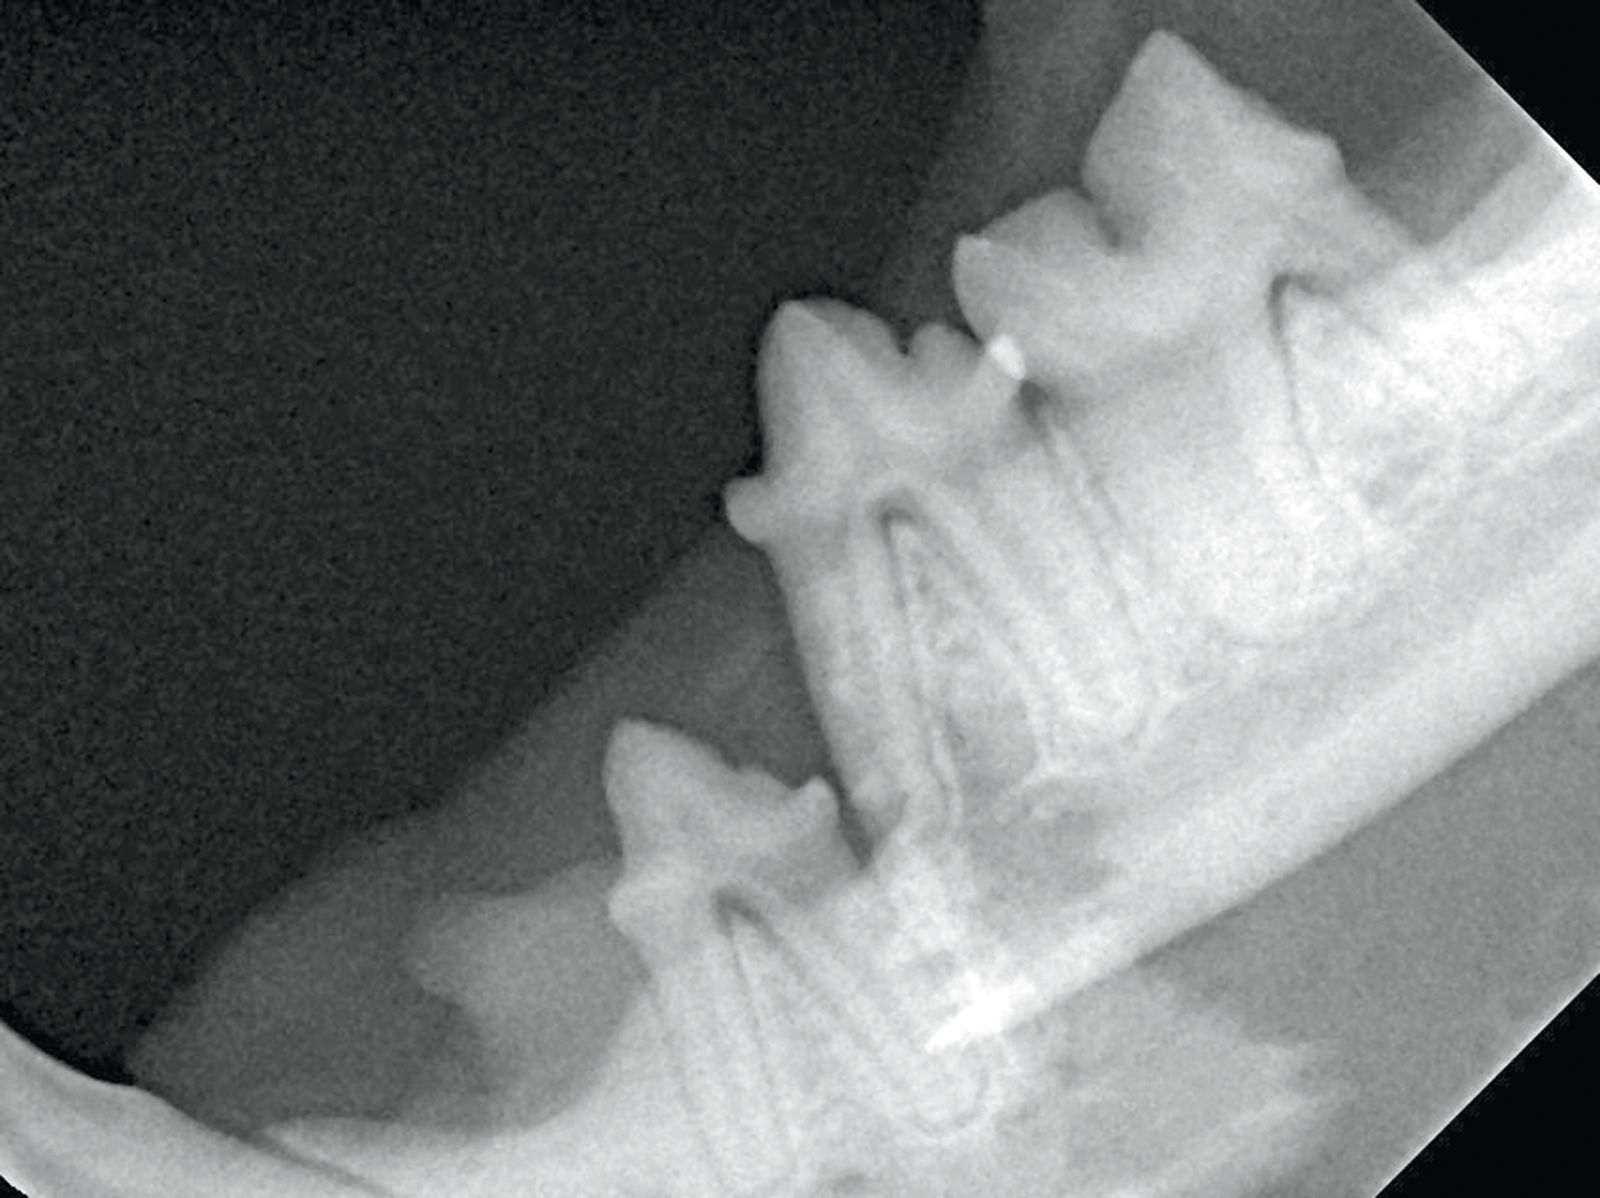

Figure 4. Fracture de la mandibule avec dplacement :a

Figure 4. Fracture de la mandibule avec dplacement :a. La partie caudale de la mandibule est tire vers la base du crne tandis que la partie rostrale est dplace ventralement. Markus Eickhoff

Figure 4. Fracture de la mandibule avec dplacement

Figure 4. Fracture de la mandibule avec dplacement :b. La radiographie montre clairement le dplacement du fragment mandibulaire. Markus Eickhoff

Figure 4. Fracture de la mandibule avec dplacement :c. La fracture a t rduite et fixe laide dune rsine acrylique et dun cerclage. Markus Eickhoff

Figure 4. Fracture de la mandibule avec dplacement :d

Figure 4. Fracture de la mandibule avec dplacement :d. Radiographie post-opratoire montrant le ralignement de la mandibule avec la rsine et les fils de cerclage. Markus Eickhoff